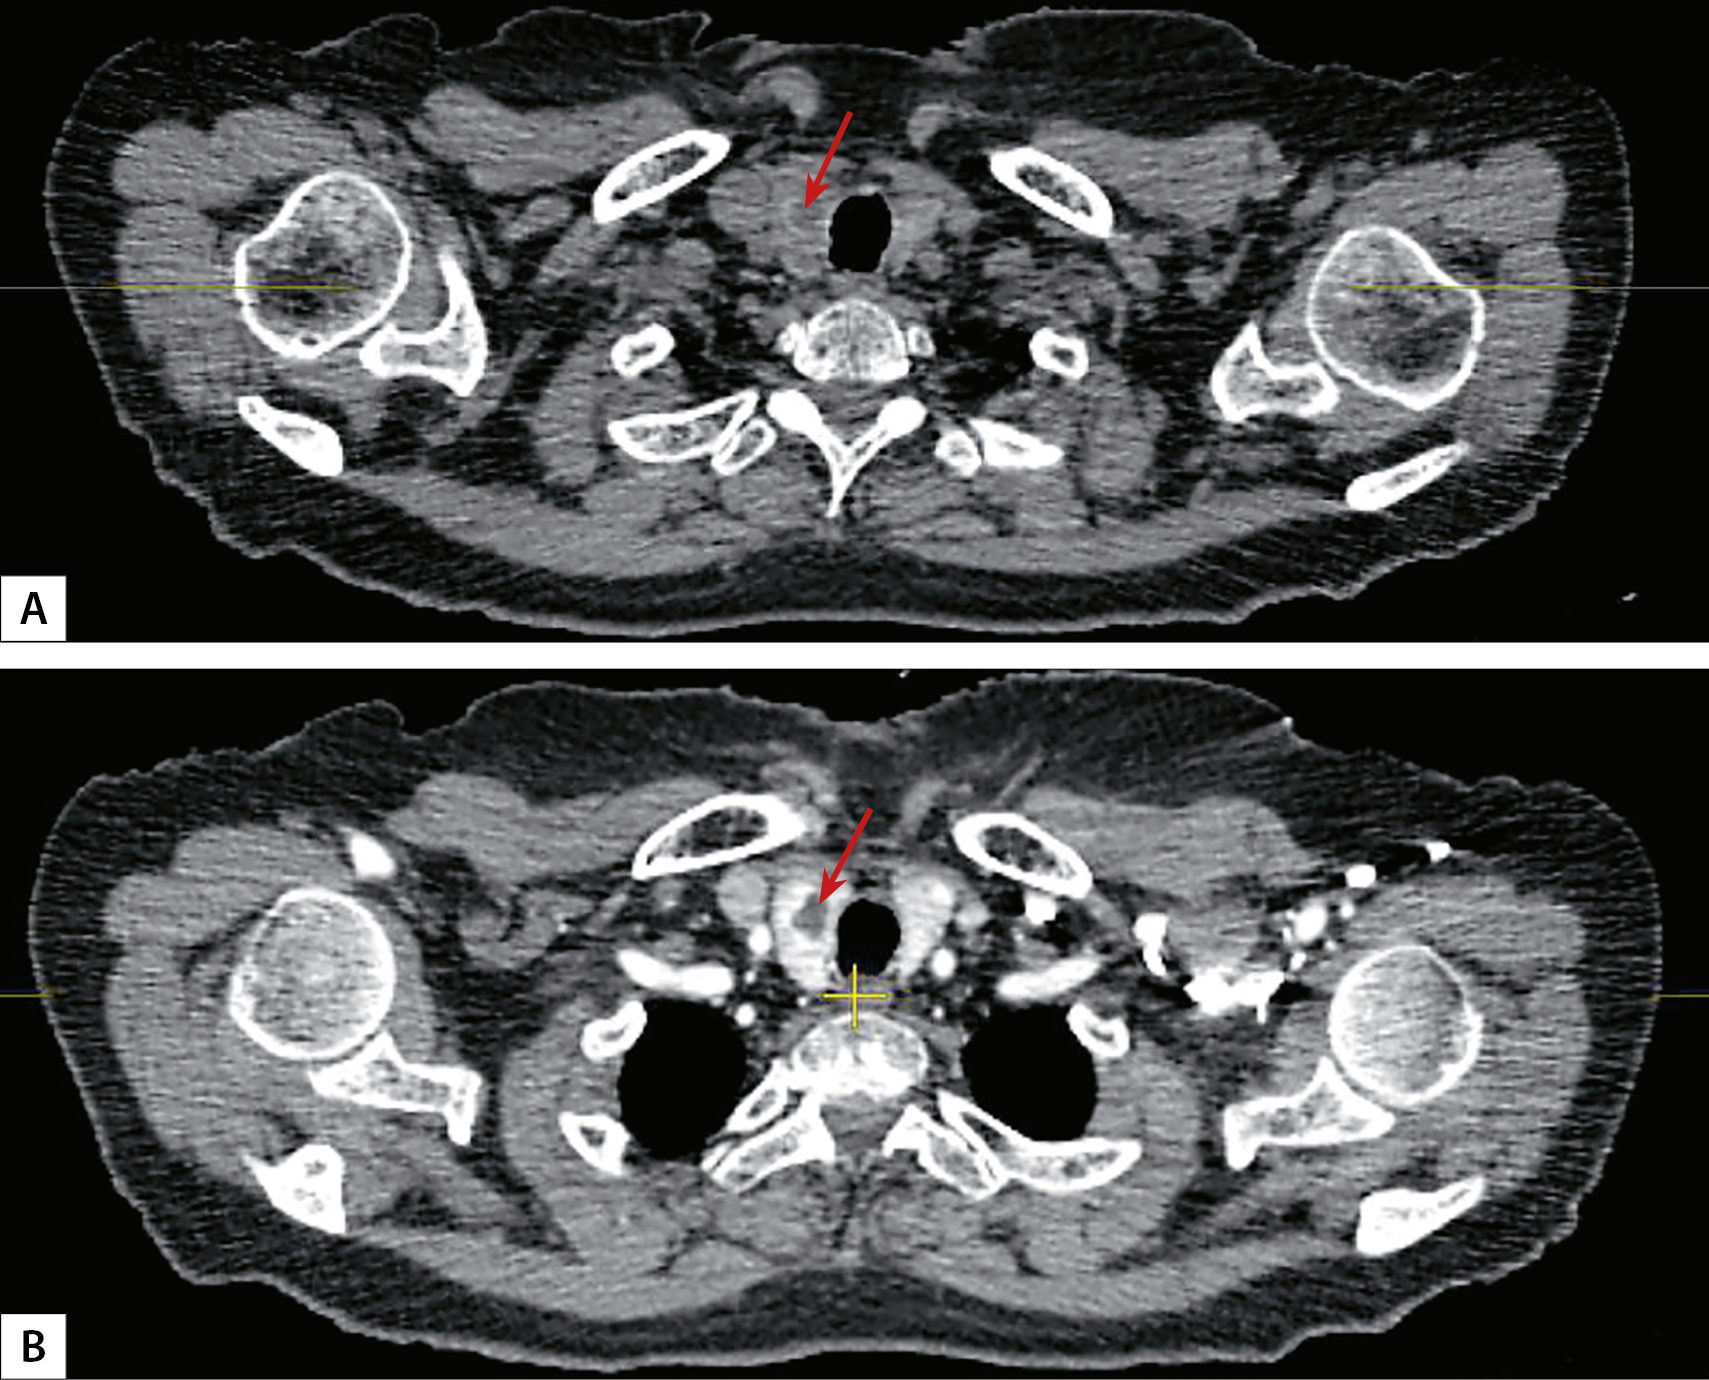

1. Рисунок 1. КТ-картина карциномы щитовидной железы (аксиальный срез, образование указано стрелкой). А — артериальная фаза, В — венозная фаза. | |